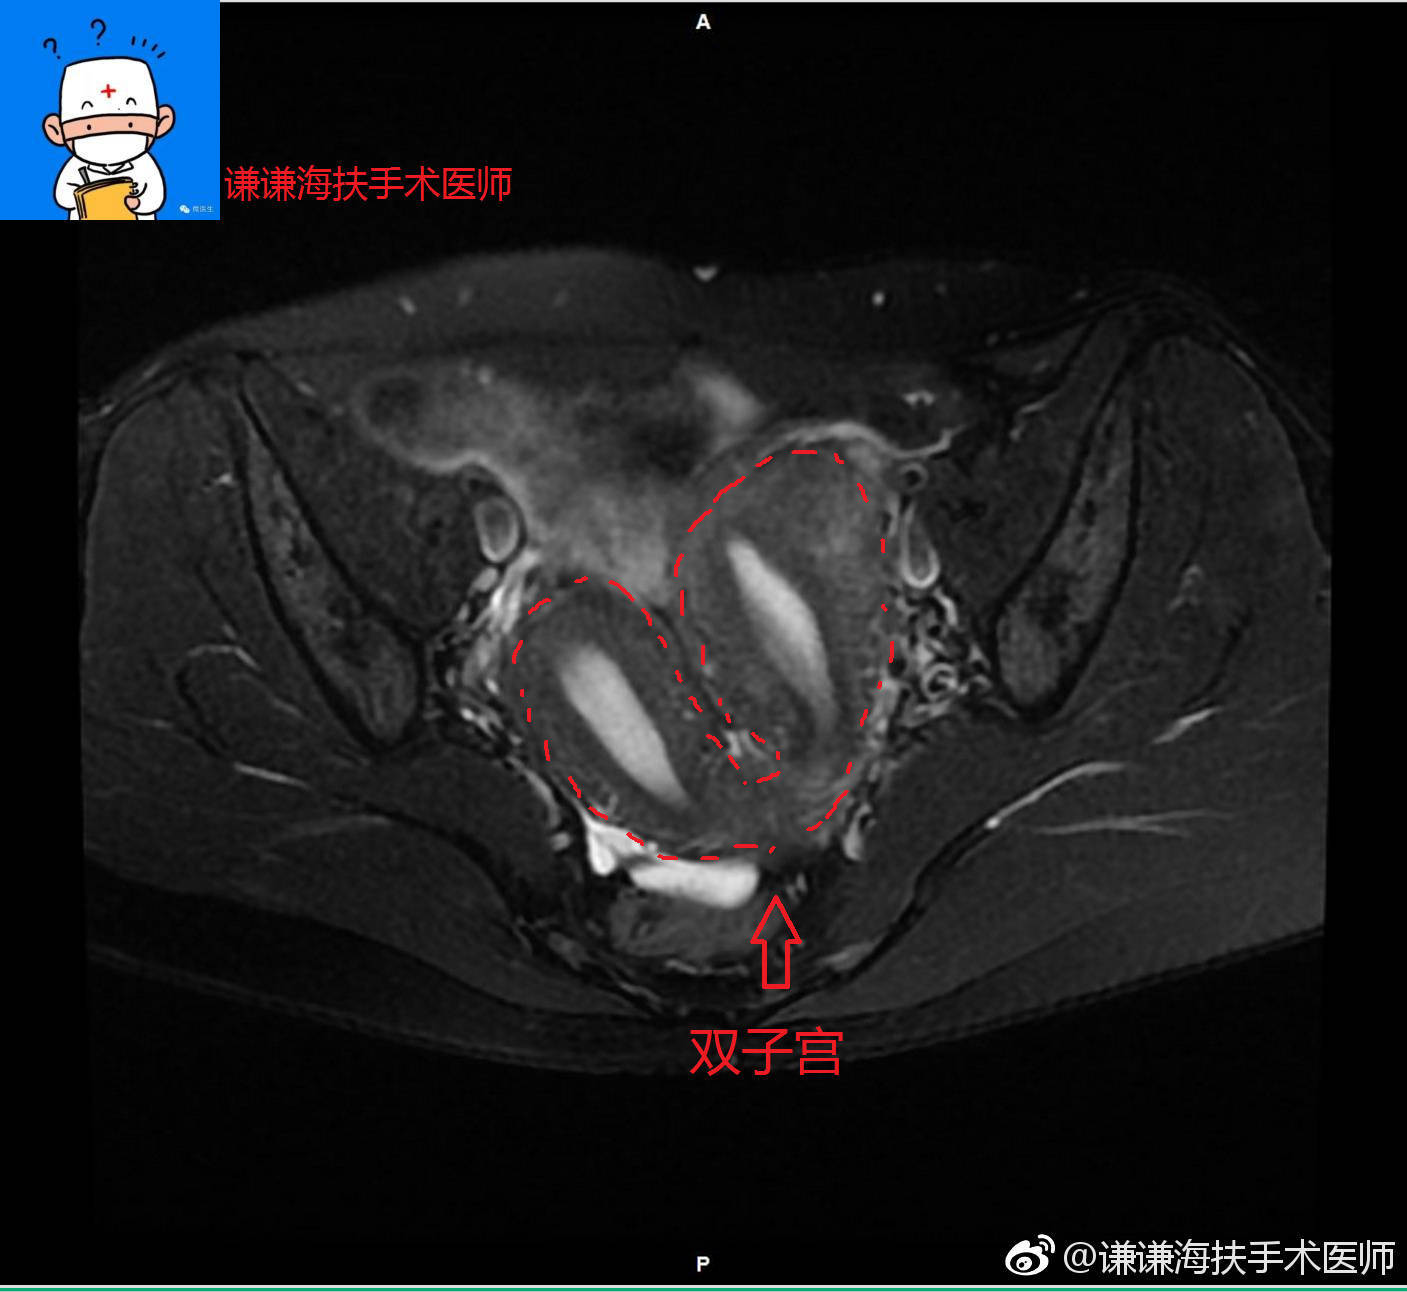

半套到底是什么意思以及双子宫是啥回事 影响怀孕和分娩吗

说到“半套”,很多朋友第一反应可能是装修或某些服务里提到的半包,但其实这个词在不同领域有不一样的意思。先聊聊医学里的“双子宫”——正常情况下,女性只有一个子宫,是由胚胎时期左右两个生殖窦慢慢融合形成的。如果这两个“半套子宫”没融合完全,就会出现双子宫情况。这种发育异常,有时候可能影响怀孕和分娩,因为子宫结构不完整可能导致孕期风险。

说白了,半套从医学角度来看,是指子宫发育不完全的状态,两边各有一个“半子宫”。而对于准妈妈们来说,这种情况确实需要多加注意医生指导,毕竟身体是不是“整套”了,关系着怀孕的顺利与宝宝的健康。

双子宫会严重影响怀孕吗?

说实话,有点复杂啦,但大多数情况下,双子宫确实可能带来一些怀孕的风险,比如流产或早产。不过,很多有双子宫的妹子依然能顺利怀孕生娃,只要注意定期看医生,听话按医嘱检查,别担心太多,都会有好结果的! -